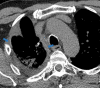

The coronavirus disease 2019 (COVID-19) pandemic is a global health care emergency. Although reverse-transcription polymerase chain reaction testing is the reference standard method to identify patients with COVID-19 infection, chest radiography and CT play a vital role in the detection and management of these patients. Prediction models for COVID-19 imaging are rapidly being developed to support medical decision making. However, inadequate availability of a diverse annotated data set has limited the performance and generalizability of existing models. To address this unmet need, the RSNA and Society of Thoracic Radiology collaborated to develop the RSNA International COVID-19 Open Radiology Database (RICORD). This database is the first multi-institutional, multinational, expert-annotated COVID-19 imaging data set. It is made freely available to the machine learning community as a research and educational resource for COVID-19 chest imaging. Pixel-level volumetric segmentation with clinical annotations was performed by thoracic radiology subspecialists for all COVID-19-positive thoracic CT scans. The labeling schema was coordinated with other international consensus panels and COVID-19 data annotation efforts, the European Society of Medical Imaging Informatics, the American College of Radiology, and the American Association of Physicists in Medicine. Study-level COVID-19 classification labels for chest radiographs were annotated by three radiologists, with majority vote adjudication by board-certified radiologists. RICORD consists of 240 thoracic CT scans and 1000 chest radiographs contributed from four international sites. It is anticipated that RICORD will ideally lead to prediction models that can demonstrate sustained performance across populations and health care systems.